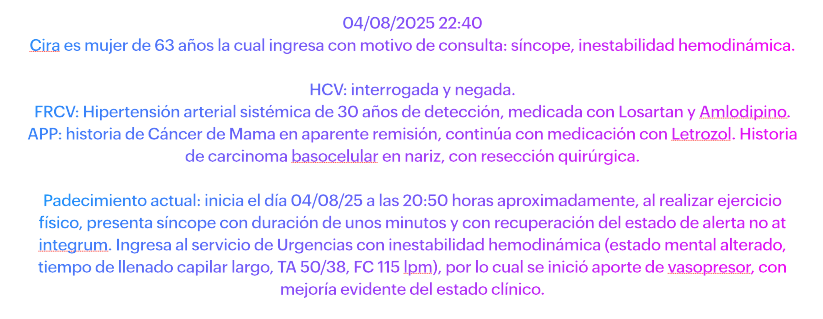

Con este material deberíamos ser capaces de poder realizar el abordaje inicial esta paciente, que se presenta al Servicio de Urgencias con motivo de consulta: Síncope.